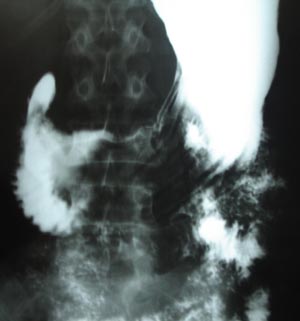

Normal Barium meal

Each part of the stomach & duodenum should be checked to ensure that no abnormal narrowing is present. A transient contraction wave must not be confused with a constant pathological narrowing.